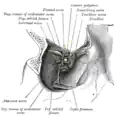

Eye movement

The movement of the eye is controlled by extraocular muscles; in humans, the six distinct muscles are the superior, an inferior, a medial and a lateral rectus, as well as a superior and an inferior oblique. The superior ophthalmic vein is a sigmoidal vessel along the superior margin of the orbital canal that drains deoxygenated blood from surrounding musculature. The ophthalmic artery is a crucial structure in the orbit, as it is often the only source of collateral blood to the brain in cases of large internal carotid infarcts, as it is a collateral pathway to the circle of Willis. In addition, there is the optic canal, which contains the optic nerve, or cranial nerve II, and is formed entirely by the lesser wing of the sphenoid, separated from the supraorbital fissure by the optic strut. Injury to any one of these structures by infection, trauma or neoplasm can cause temporary or permanent visual dysfunction, and even blindness if not promptly corrected.[10] The orbits also protect the eye from mechanical injury.[5]

Dissection showing origins of right ocular muscles, and nerves entering by the superior orbital fissure

Dissection showing origins of right ocular muscles, and nerves entering by the superior orbital fissure -